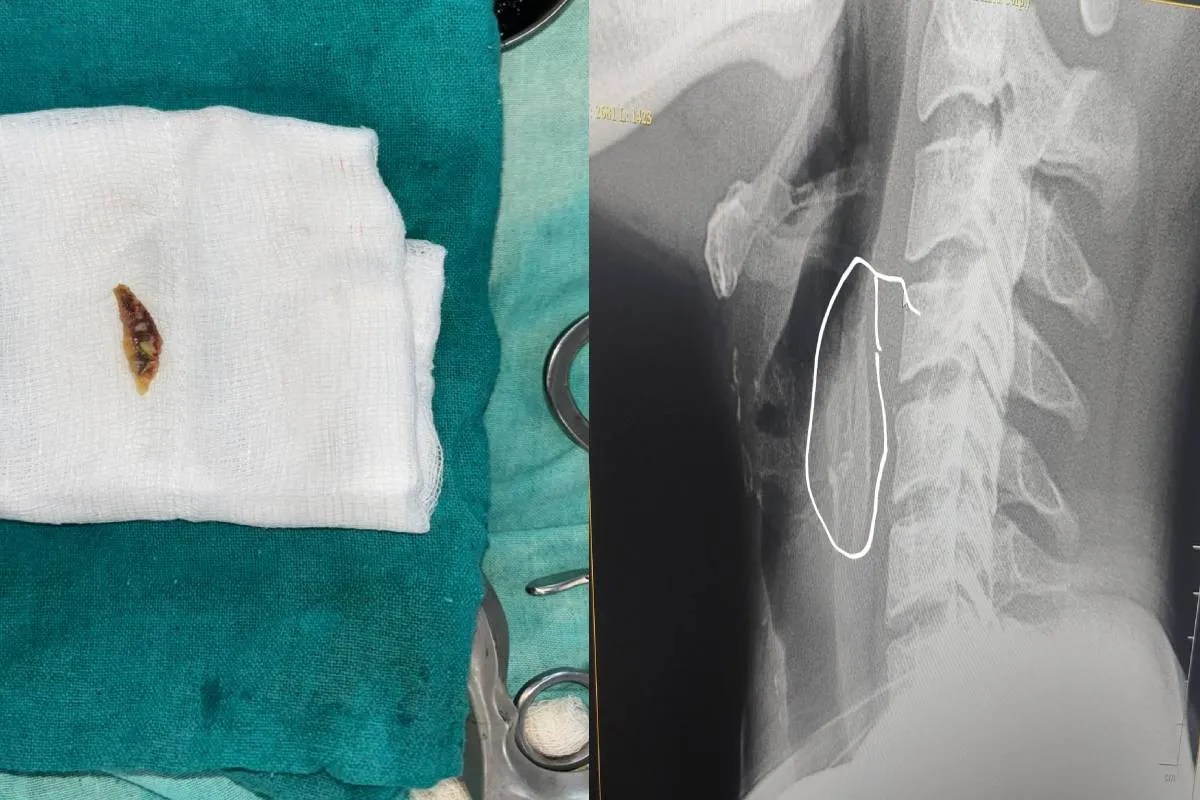

कन्हैया लाल के पिता दशरथ ने बताया कि वो कांच इलाके में रहते हैं। रविवार रात को चिकन खा रहे थे तभी अचानक हड्डी बेटे कन्हैया के गले में अटक गई। इसके बाद कन्हैया को सांस लेने, बोलने और कुछ भी निगलने में भारी दिक्कत होने लगी। वो दर्द से छटपटाने लगा तो उसे तुरंत शाजापुर जिला अस्पताल लेकर आए, जहां जांच करने पर डॉक्टरों ने बताया कि गले में चिकन की हड्डी फंस गई है। अस्पताल में तैनात ईएमटी डॉक्टर तेजपाल सिंह जादौन ने मामले की गंभीरता को समझते हुए तत्काल ऑपरेशन करने का निर्णय लिया। सावधानीपूर्वक की गई इस प्रक्रिया के बाद गले में फंसी हड्डी को सफलतापूर्वक बाहर निकाल लिया गया।

ऑपरेशन के बाद मरीज कन्हैया लाल की हालत में तेजी से सुधार हुआ और अब वह खतरे से बाहर बताए जा रहे हैं। कन्हैया लाल ने बताया कि रविवार रात को हड्डी फंसने के बाद उन्हें असहनीय दर्द और घुटन महसूस हो रही थी। सोमवार को जिला अस्पताल के डॉक्टरों और स्टाफ की तत्परता से उन्हें राहत मिली। परिजनों ने डॉक्टर तेजपाल सिंह जादौन और अस्पताल प्रशासन का आभार व्यक्त किया। अस्पताल में तैनात ईएमटी डॉक्टर तेजपाल सिंह जादौन ने आम जनता से अपील की है कि भोजन करते समय विशेष सावधानी बरतें। उन्होंने यह भी कहा कि इस तरह की किसी भी आपात स्थिति में तुरंत नजदीकी अस्पताल पहुंचें, ताकि समय पर उचित उपचार मिल सके और गंभीर परिणामों से बचा जा सके।